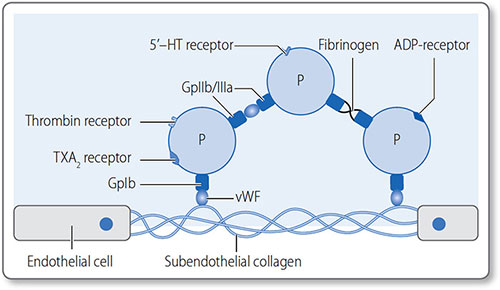

A number of platelet agonists trigger specific pathways of platelet activation, resulting in activation of the GPIIb/IIIa complex. Platelet aggregation is initiated by exposure to subendothelial components in the extracellular matrix (ECM). von Willebrand factor (vWF), a circulating protein, binds to both ECM collagen and to platelet surface glycoprotein GpIb (Figure 1.39). This results in translocation of glycoprotein complex IIb/IIIa (GpIIb/ IIIa) to the platelet surface. Platelets aggregate by bonding via GpIIb/IIIa complexes.

Figure 1.39: Platelets constitutively express GpIb on their surface, but once activated they express GpIIb/ IIIa, which mediates strong bonds between them. Gp, glycoprotein; P, platelet; TXA2, thromboxane; vWF, von Willebrand factor.